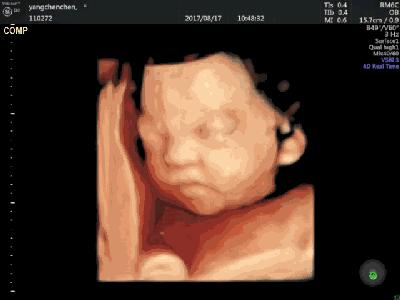

胎儿到了7个月大的时候,鼻子基本发育完成,此时宝宝的鼻孔已经可以和外界沟通了,也就是开始有嗅觉了哦~

① 宝宝的触觉:准妈妈在孕7-8周的时候,宝宝就对触觉有了反应,等到孕10周时,就开始有了明显的反应啦。

② 宝宝的味觉:孕12周后,宝宝就会吞咽羊水了,此时因为羊水中有准妈妈吃的食物的味道,宝宝也会通过吞咽羊水,而尝到食物的味道了哦~

③ 宝宝的听觉:准妈妈在孕24周左右,宝宝就可以听到外界的声音了,并且声音越大,宝宝的反应也会越强烈哦~

④ 宝宝的视觉:在孕前27周时,宝宝的大眼睛一直都处在闭合的状态,但过了27周后,宝宝就能睁开眼睛,并眨眼哦,萌萌哒~